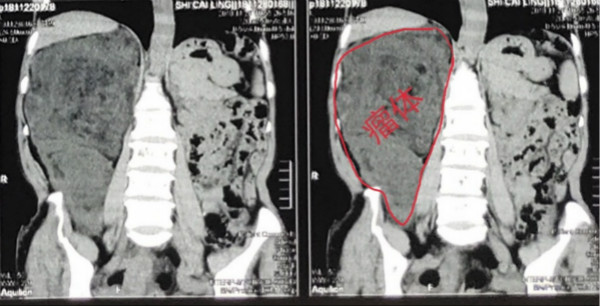

近日,一位来自甘肃省庆阳市的巨大腹膜后肿瘤患者在我院普通外科实施了手术,切除了重达6.5kg,大小28cm×21cm×25cm的脂肪肉瘤,这也是至今为止普外科罕见并顺利切除的腹膜后巨大肿瘤,目前患者已康复出院。

这是我在普外科轮转工作中遇到的第一位患者:中年女性,焦虑、无助,不安的眼神中流露出热切的期盼……,因“腹胀2个月”曾在外院就诊,行上腹部CT检查结果示:腹腔内可见一巨大团块状混杂稍低密度灶,范围巨大,考虑脂肪肉瘤可能性大。辗转几家医院均表示手术困难太大,恢复情况难以预料。患者及家属忧心忡忡,几经周折来到了我院普通外科主任陈熹教授的面前,陈主任了解情况后,细心的询问患者病情并安抚患者及随行家属的紧张情绪,随后将病人收入住院。